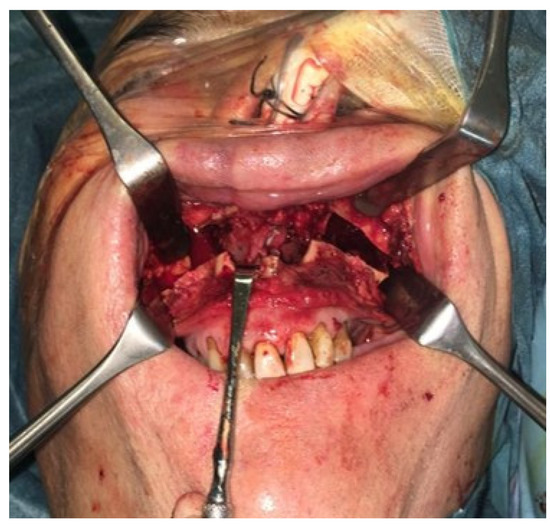

In 2022, after 2 years of sobriety, the patient underwent surgical intervention for palate reconstruction. Under general anesthesia, the surgery was performed, starting with a Le Fort I osteotomy preceded by preplating to achieve the correct repositioning of the fragment. A careful dissection of the nasal and palatal mucosa was performed after the down fracture. A temporalis muscle rotation flap was harvested on the left side (Figure 2). The operation lasted three hours in the oro-tracheal tube. A nasogastric tube was placed and kept in place for seven days with standard antibiotic and anti-inflammatory therapy. The patient was discharged after four days.

Figure 2. (A) The surgery was performed using a Le Fort I osteotomy preceded by preplating to achieve the correct repositioning of the fragment; a careful dissection of the nasal and palatal mucosa was performed after the down fracture. (B,C) Temporalis muscle harvesting and rotation (D,E) fixation of the maxillary fragments.